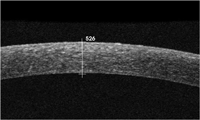

En los casos de pacientes con disfunción endotelial se realiza una DSAEK/DSEK o DMEK. La mayoría de estos pacientes están afectados por distrofias endoteliales, mayormente la distrofia de Fuchs, también traumatismos corneales, fallo de un injerto y la queratopatía bullosa. En la DSEKse realiza la técnica manualmente y se obtiene un lecho de estroma-MD-endotelio que puede variar de espesor en función de la profundidad. Vemos un ejemplo en la

Figura 9, donde observamos un lecho de 50 micras de espesor, con un total de 561 micras. Un resultado más que óptimo. En otros casos puede ser dificultoso obtener el lecho lo más fino posible como es el caso de la

Figura 9. DSEK con injerto de 50 m.